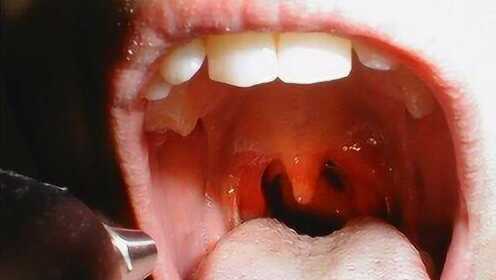

慢性咽炎概述

慢性咽炎是一種常見的喉部疾病,主要表現(xiàn)為咽部不適、干燥、瘙癢、疼痛等癥狀,由于長期受到刺激或感染,咽部黏膜出現(xiàn)慢性炎癥表現(xiàn),慢性咽炎雖然不是嚴(yán)重疾病,但癥狀反復(fù)發(fā)作,嚴(yán)重影響患者的生活質(zhì)量。